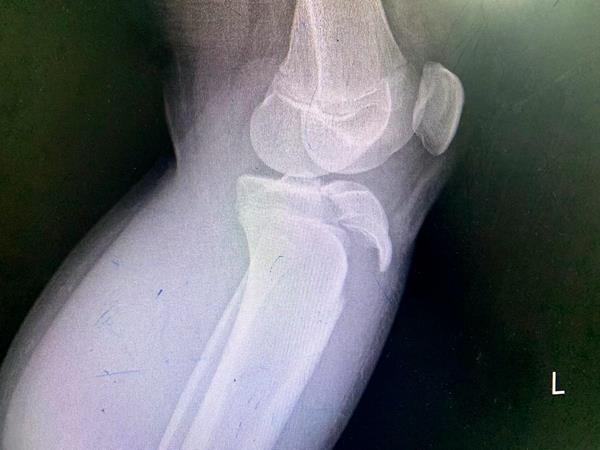

患者脛骨結(jié)節(jié)撕脫骨折影像

這次收治的患者屬于Ogden 3A型,手術(shù)指征明確,手術(shù)團隊采用骨折端切開復位空心釘內(nèi)固定+髕韌帶可吸收錨釘重建術(shù)+經(jīng)膝關(guān)節(jié)鏡探查、清理的手術(shù)方式,獲得滿意效果。